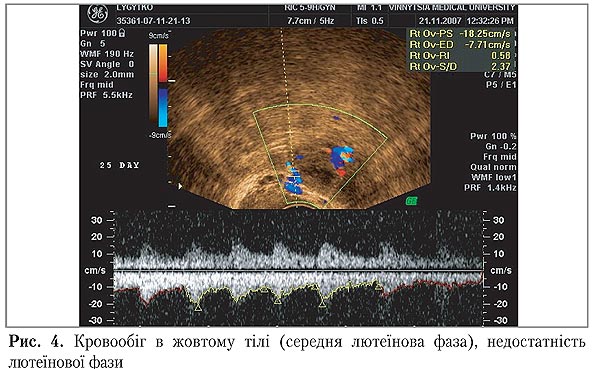

Натомість, у жінок з НЛФ середні величини судинного опору, зокрема, індекс резистентності, достовірно перевищував показники при фізіологічних циклах і залишався стабільно високим протягом всієї лютеїнової фази на тлі знижених показників МСС (рис. 4).

Швидкість кровообігу в судинах жовтого тіла у жінок з НЛФ в середню лютеїнову фазу хоча і булла вище, ніж в преовіляторному фолікулі, але не перевищувала 12 см/с, в той час як в групі здорових жінок її значення коливались у межах 16–20 см/с (табл. 3)